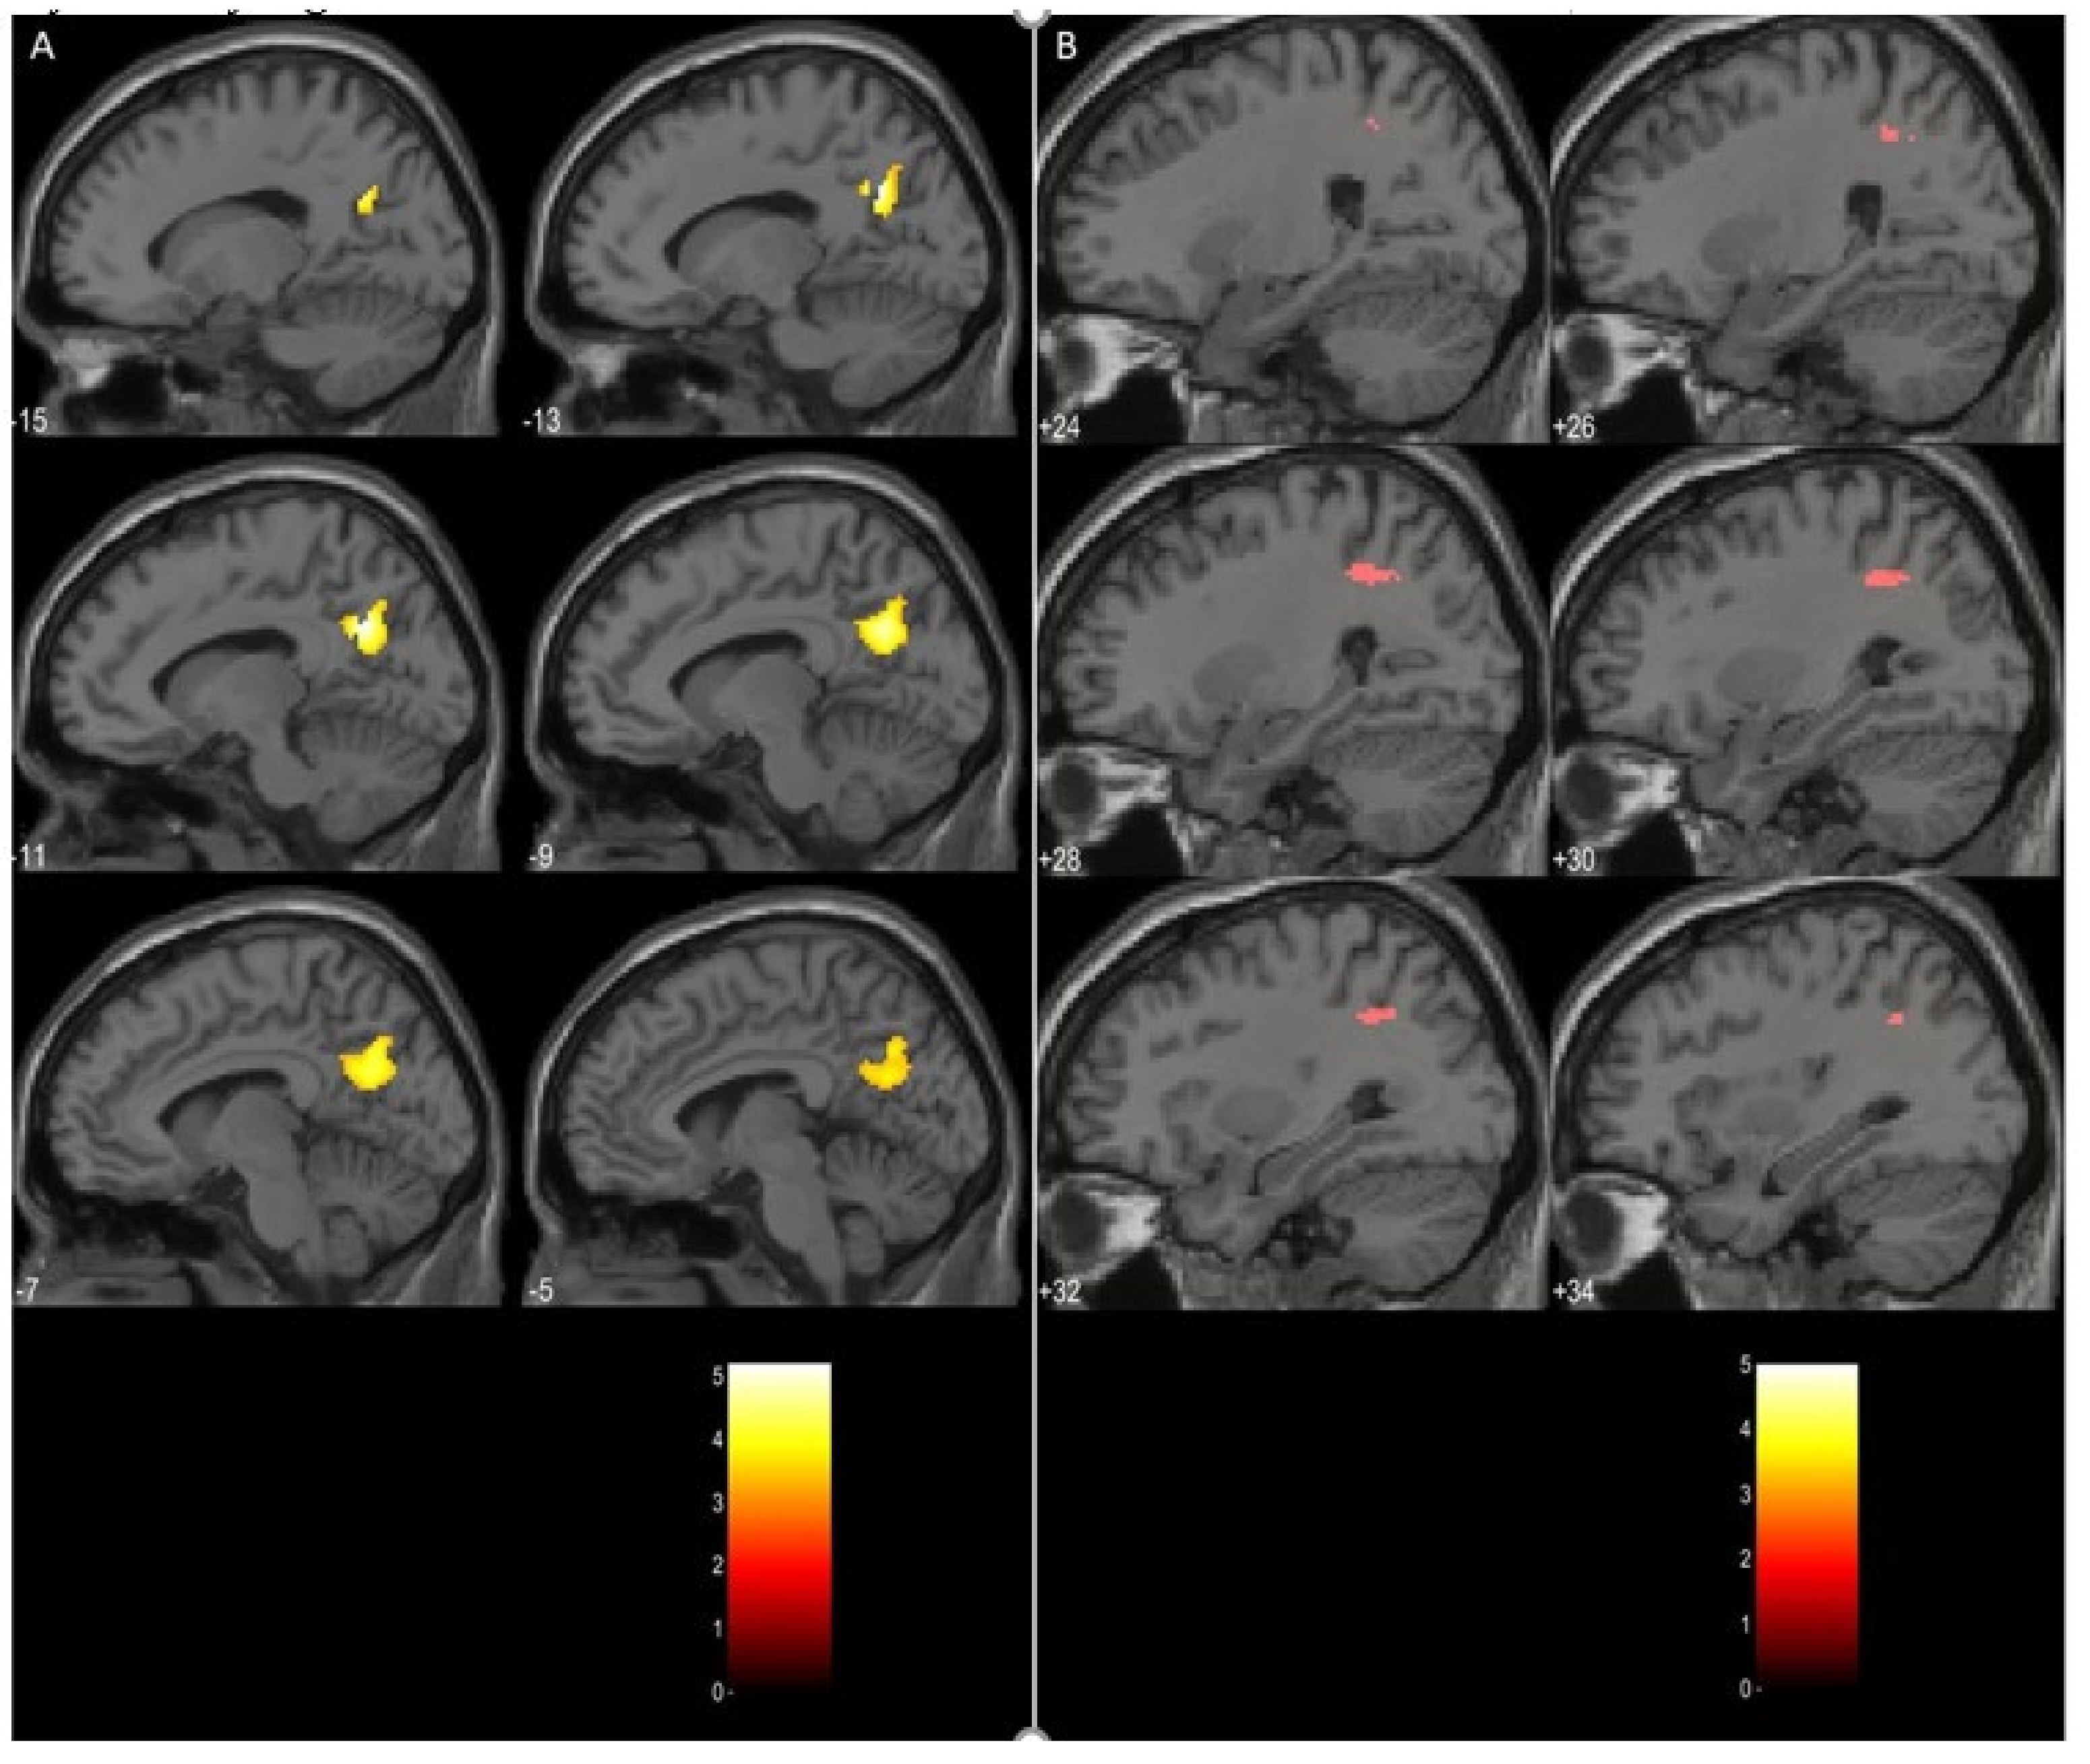

3.3. Task Related Data Analysis